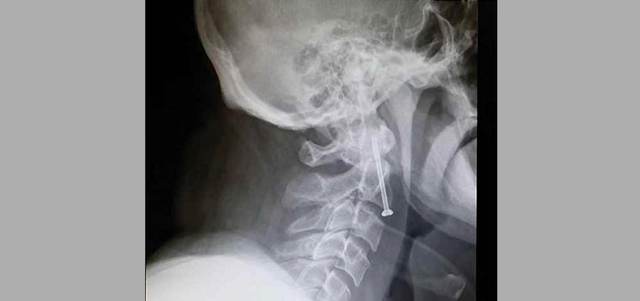

أجرى فريق من الأطباء المتخصصين في الجراحة العصبية عملية جراحية دقيقة، لمواطن يبلغ من العمر 45 عاماً، تعرض لإصابة عمل، جرى خلالها تثبيت الفقرة العنقية الثانية لإنقاذه من الشلل الرباعي.

وكان المواطن تعرض لضربة قوية على مؤخرة الرأس من حاوية بضائع أثناء عمله في الميناء، الأمر الذي أدى إلى فقدانه الوعي، وتم نقله إلى أقرب مستشفى، وبعد إجراء الفحوص وصور الأشعة تبين وجود كسر في الفقرة الثانية من العمود الفقري الرقبي، وتبين أنه يحتاج الى جراحة عاجلة لتثبيت الفقرة العنقية، وهو ما لم يتوافر في المستشفى، واقتُرح على المريض حل علاجي تحفظي، يعتمد على ارتداء طوق يمتد من الرأس حتى الكتفين لمنع تحريك الرأس لمدة ستة أشهر، لكنه رفض.

وللمرة الثانية نقل المريض إلى المستشفى السعودي الألماني، وبحسب الفريق الطبي الذي أجرى العملية، فإن الكسر تسبب في عدم ثبات الفقرة العنقية الثانية، ما شكل خطراً على النخاع الشوكي، حيث إن الحركات البسيطة من الممكن أن تصيبه بالشلل الرباعي.

وبادر الفريق الجراحي إلى إجراء جراحة عاجلة بإدخال مسمار لتثبيت الفقرة باستخدام جهاز الملاحة في الجراحة العصبية، الذي يمكن الطبيب من رؤية واضحة ودقيقة تضمن أفضل النتائج وبدقة عالية من جوانب عدة، ويبعد خيار الجراحة التقليدية وما تحمله من مخاطر، وتعافى المريض بعد يوم واحد من الجراحة، وأصبح قادراً على السير مرتدياً طوقاً للرقبة، يضمن حمايتها وتقييد حركتها لفترة محددة لضمان سرعة التعافي.